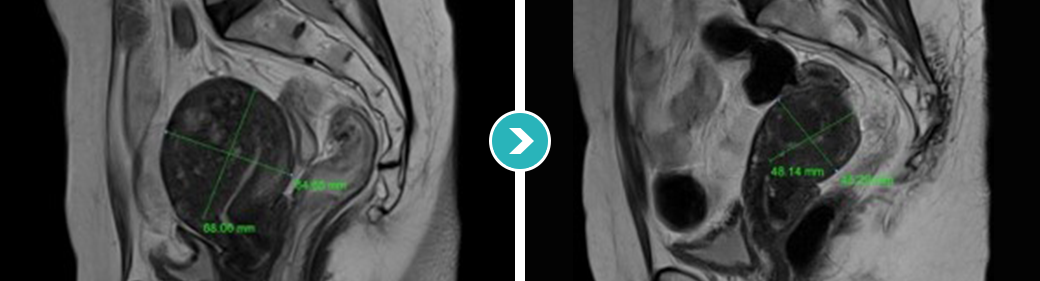

3STEP HIFU PROGRAM 2010년 부터 오직 자궁근종과 자궁선근증의 안전한 치료를 위해 전 과정MRI통합 하이푸 치료 프로그램 운영

시술 전 악성화 병변으로의 변화의 가능성 확인 및 숨어있는

악성 병변을 분석하는 MRI 촬영

시술과정 초음파영상과 MRI영상 콜라보 모니터링

시술 후 하이푸 치료 브리핑 및 객관적 평가

MRI촬영으로 자궁근종의 상태(위치, 개수, 크기, 모양 등), 자궁근종의 혈액공급 및 혈류,

자궁근종과 인접한 주요장기 및 구조, 초음파 발사경로의 확보 등을 분석함. 또한, 정밀초음파는 제거할 자궁근종의 개수, 자궁근종의 치료 슬라이스 수와

각 슬라이스의 체적, 근종제거마진, 근종과 인접한 장기와의 상관관계 등을 분석합니다.

전사적으로 시행함으로써 하이푸 시술의 안전도와 치료효과를 높이는 통합 MRI하이푸 프로그램입니다.

시술 전 MRI검사 결과를 바탕으로 자궁근종이나

자궁선근증 등 종양의 위치, 크기, 모양 등 정확하게 파악

자궁선근증을 4가지 형태(경화형, 결절형, 낭종형, 분산형)로 분류할 수 있으며

각 유형의 맞춤 차별적 시술을 진행합니다.

자궁선근증은 환자에 따라 다양한 크기와 유형을 보이기 때문에 하이푸 시술 전에

정확한 치료플랜과 주변 조직에 영향을 주지 않는 정밀한 시술법이 요구됩니다.